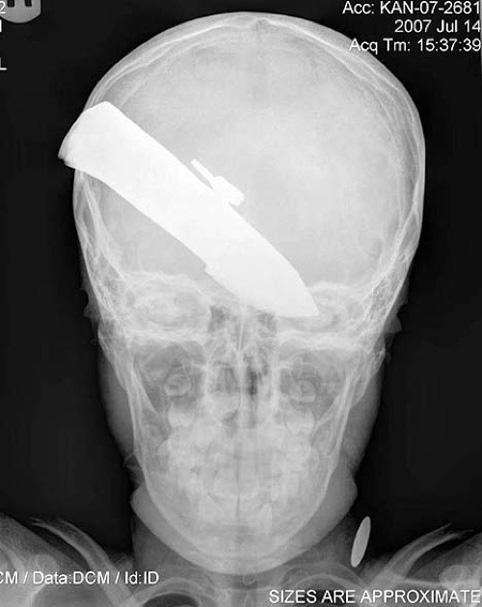

Толгойдоо 17 жил хутгатай явжээ

Сальвадорын нэгэн эмнэлэгт удаан хугацаатай үргэлжилсэн мэс заслын үеэр өвчтөний тархинаас 9 см урт хутганы ир гаргаж авсан байна. Гуталчнаар ажилладаг түүн рүү бүр 1995 онд хэсэг мансуурагчид халджээ. Тэд мэдээж гуталчны цавууг булааж авахаар дайрахад гуталчин эсэргүүцэж зодоон болсон байна.